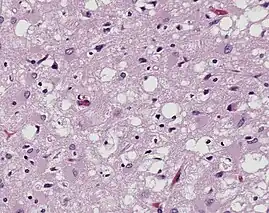

Prions are misfolded proteins that are transmissible and can influence abnormal folding of normal proteins in the brain. They do not contain any DNA or RNA and cannot replicate other than to convert already existing normal proteins to the misfolded state. These abnormally folded proteins are found characteristically in many neurodegenerative diseases as they aggregate the central nervous system and create plaques that damages the tissue structure. This essentially creates "holes" in the tissue. It has been found that prions transmit three ways: obtained, familial, and sporadic. It has also been found that plants play the role of vector for prions. There are eight different diseases that affect mammals that are caused by prions such as scrapie, bovine spongiform encephalopathy (mad cow disease) and feline spongiform encephalopathy (FSE). There are also ten diseases that affect humans, such as Creutzfeldt–Jakob disease (CJD)[19] and Fatal familial insomnia (FFI).